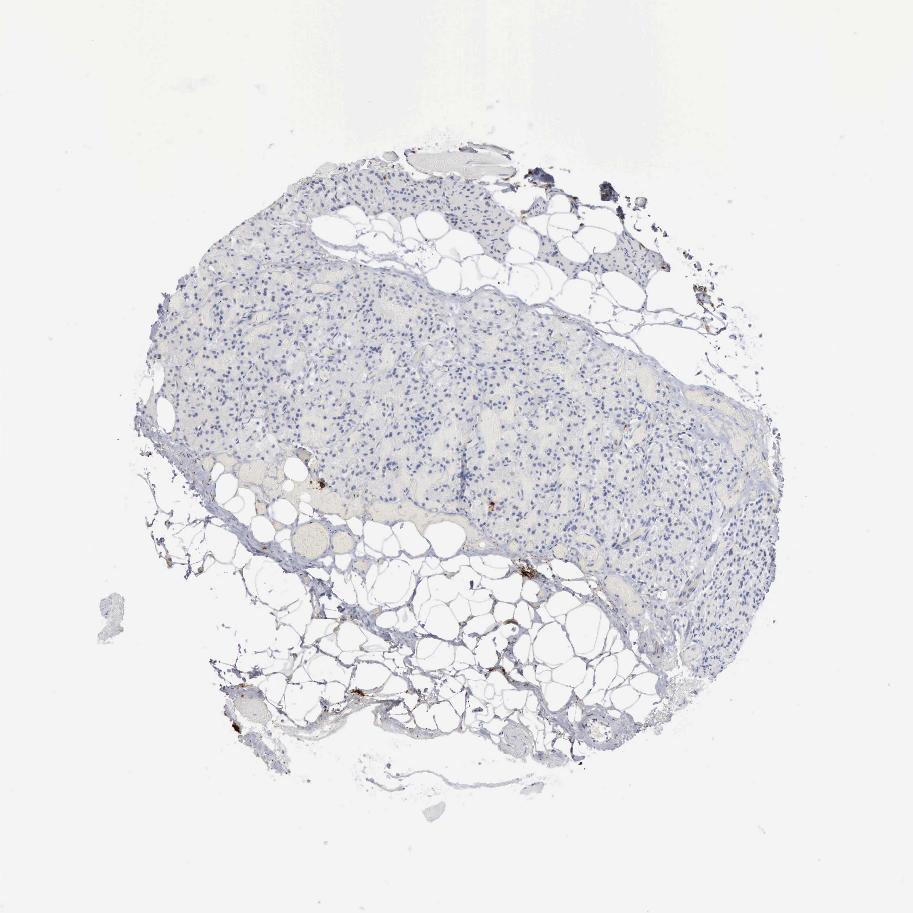

TISSUE PRIMARY DATA PARATHYROID GLAND Show tissue menu

PARATHYROID GLAND - Antibody stainingi

Antibody staining in the annotated cell types in the current human tissue is reported as not detected, low, medium, or high, based on conventional immunohistochemistry profiling in selected tissues. This score is based on the combination of the staining intensity and fraction of stained cells.

Each image is clickable and will lead to virtual microscopy that enables deeper exploration of all samples and also displays staining intensity scores, fraction scores and subcellular localization as well as patient and tissue information for each sample.

Antibody HPA052634Antibody CAB000363

Glandular cells Not detectedNot detected